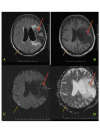

Figure 1. Magnetic Resonance Imaging (MRI) of the Brain Showing Current and Previous Infarction Sites (Panels A-D)

Magnetic resonance imaging (MRI) of the brain showing an acute right-sided parietal lobe infarct (shown with yellow arrows) and an old left-sided middle cerebral artery territory infarct (shown with red arrows) in a 63-year-old patient [9].